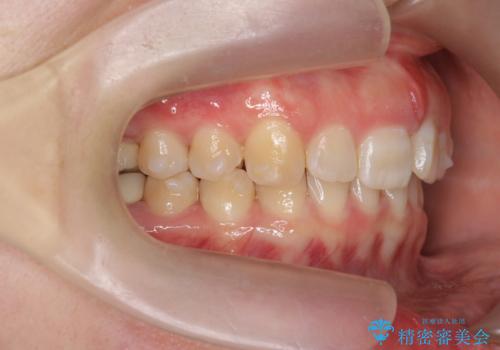

ねじれた前歯を改善するマウスピース矯正

- 大きくねじれた前歯をまっすぐに並べたい。と矯正治療を希望され来院されました。

前歯をきっちり並べるには奥歯の噛み合わせの調整を行い上下の前後的関係を治し、ねじれを取るスペースを確保していきます。

当初前歯だけ治れば良い、という心算で来院されましたが奥歯の噛み合わせも負担が大きく問題の起きやすいことをお伝えし上顎の奥歯をきっちりと後方移動行い噛み合わせの調整を行いました。・